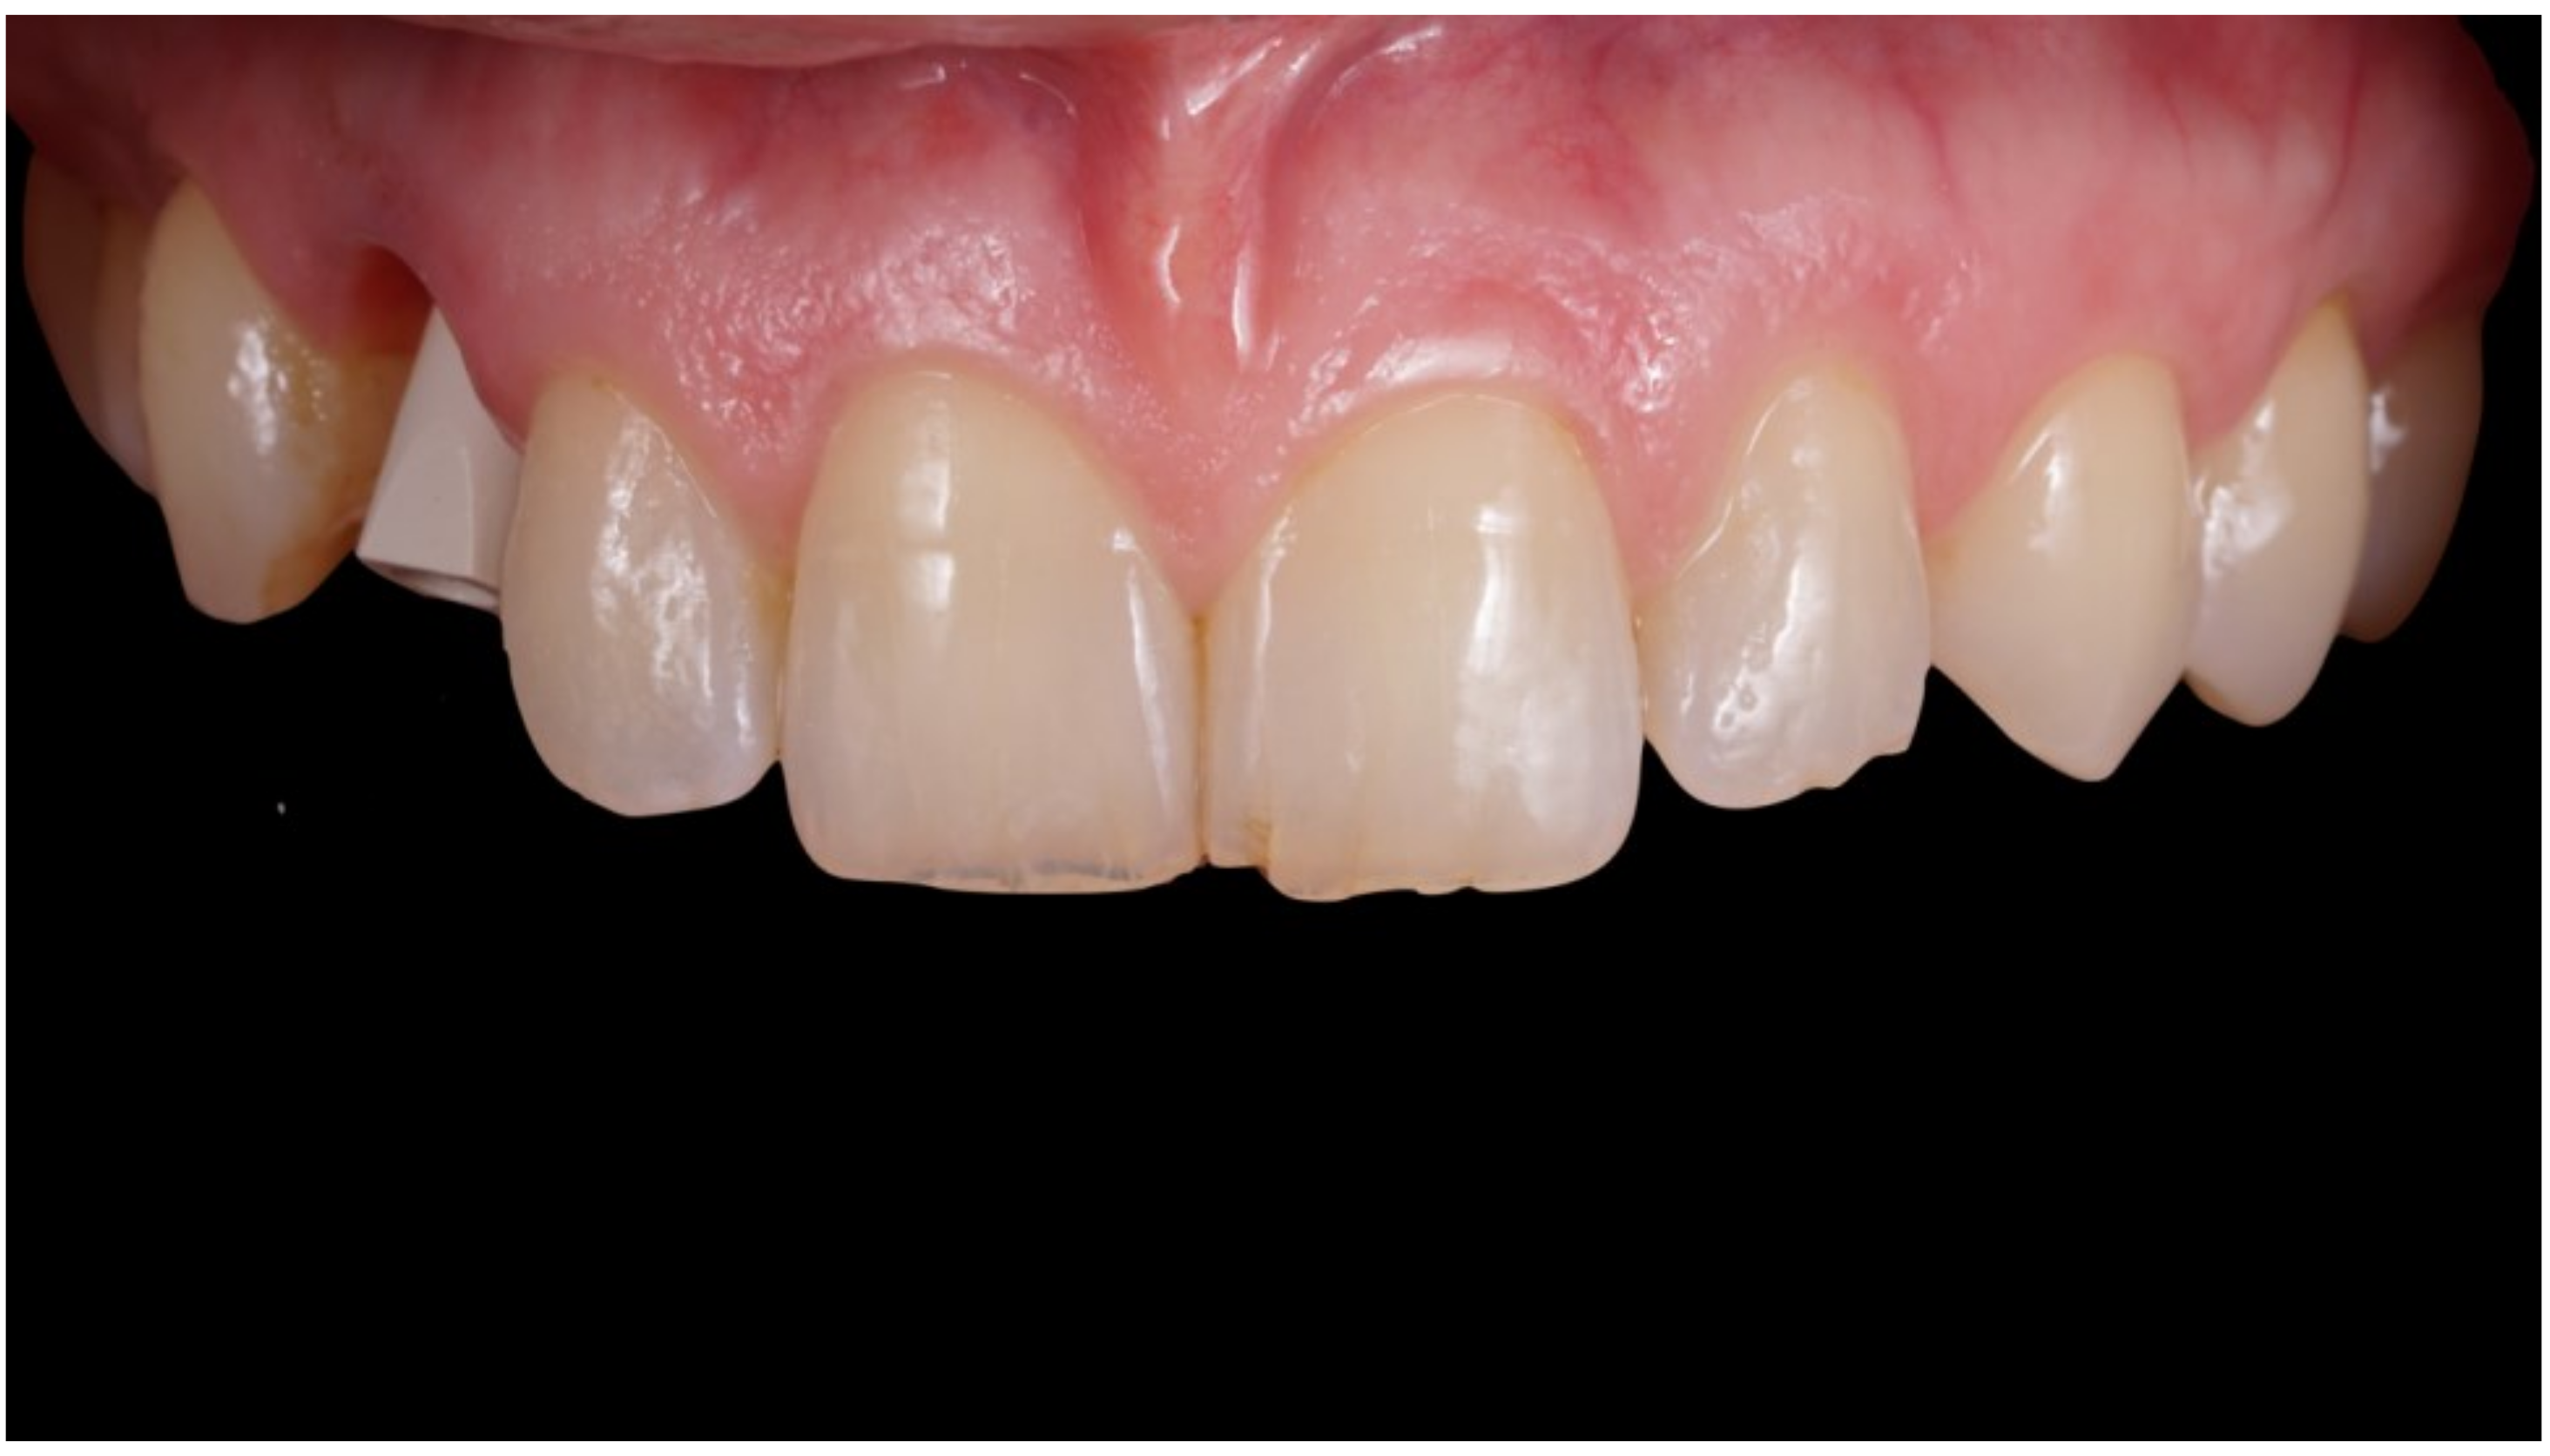

Figure 8.

Delivery of final crown.

Definitive crown after 1 year of follow-up, frontal view.

Figure 10.